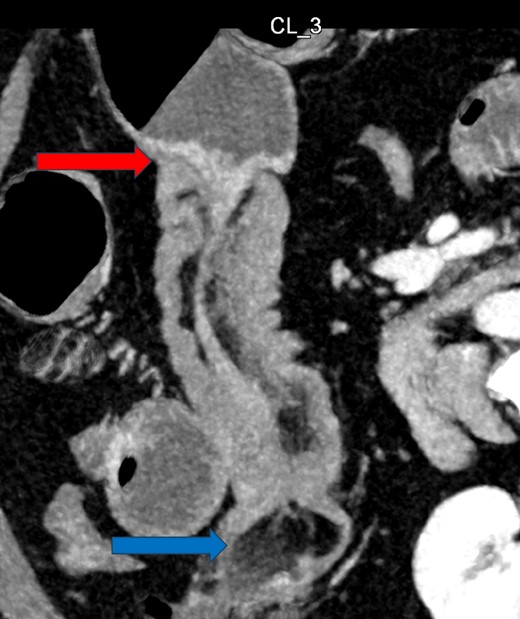

Given her abdominal symptoms and signs, she was subjected to an abdominal X-ray (Fig. 1), which showed multiple distended loops of the small bowel, and a chest X-ray, which showed left basal atelectasis. A working diagnosis of SBO was made. She was put nil by mouth. A nasogastric tube and a urinary catheter were inserted. After initial resuscitation, she was subjected to CTAP with contrast. The findings of the CTAP were in keeping with acute distal SBO secondary to an ileo-ileal intussusception. No obvious mucosal mass was stated in the initial report (Figs 2 and 3).

CT scan of abdomen: oblique coronal view of abdomen showing intussusception with low attenuation lesion distally C/W a lipoma (arrow).

CT Abdomen: MPR reconstruction of the plane of intussusception showing a distal lipoma and proximal start of intussusception.